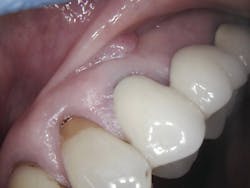

Aiming the laser at the affected area at a 45-degree angle, the first step was to remove the fibroma (figure 3). This was done easily after choosing the appropriate spot size, mist, and power. Following removal, the selections were adjusted for the next step, which was to make an incision in the gingiva. Keep in mind that it was vital to leave approximately 2 mm of keratinized tissue and raise the flap at this time. The laser’s precision allowed for the precise cutting that was needed.

From a patient perspective, a 9.3 µm CO2 laser can dramatically change the dental experience. In this case, chair time was reduced (compare 40 minutes using the laser to the 60–90 minutes required by traditional dentistry), and the patient did not have to worry about excessive blood or postoperative pain. Healing was also rapid without any gingival defects.

During post-op visits, final results at the three- and eight-month marks and x-rays taken at eight months revealed optimal outcomes that met the clinical objective (figures 8–10).